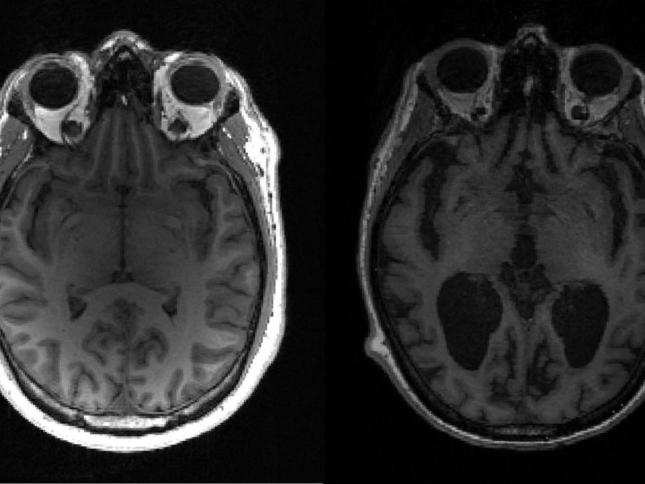

يقدم هذا الفحص الطبي قراءة لشيفرة الورم الجينية بأكملها لدى المريض ويحدد كل الطفرات الجينية المسببة للسرطان